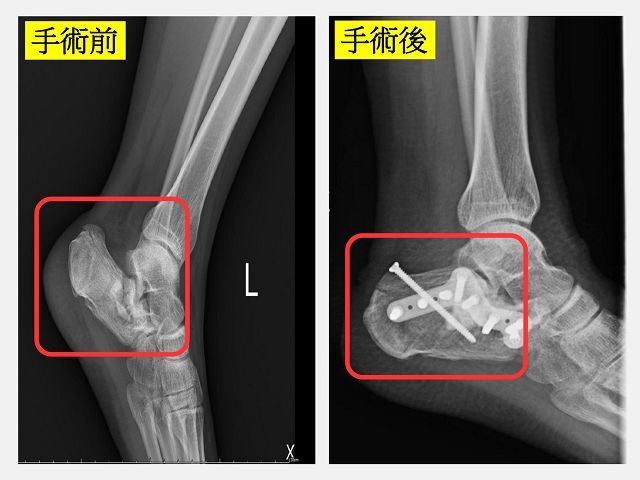

18歲少女小君在便利商店上班,下班騎機車回家時因為太累了發生自摔車禍,左腳整個扭曲變形痛到快休克,躺在地上不能動彈。路人急忙叫救護車將小君送到仁愛長庚合作聯盟醫院的急診室搶救。急診醫師安排X光發現小君的左腳跟發生了粉碎性骨折。在骨科部長黃贊文醫師的安排下,會同劉永川主任及林口長庚外傷骨科蔡秉叡醫師一同重建小君的左腳。在歷經3個月的治療和復健後,小君終於擺脫輪椅和拐杖回到日常生活。

林口長庚外傷骨科蔡秉叡醫師說,跟骨骨折可分為關節內或關節外的骨折,關節內的跟骨骨折要進行復位固定手術的難度較高。傳統手術方式會開較大的傷口,手術視野大要進行復位及固定較容易但可能也會有較多的傷口癒合問題。本次手術使用微創跗骨竇(sinus tarsi)方式,利用微創的傷口完成關節內粉碎性骨折的復位、植骨支撐塌陷後的跟骨及鋼板固定骨折,這樣的微創手術對軟組織的傷害比較小,併發症也比較少。